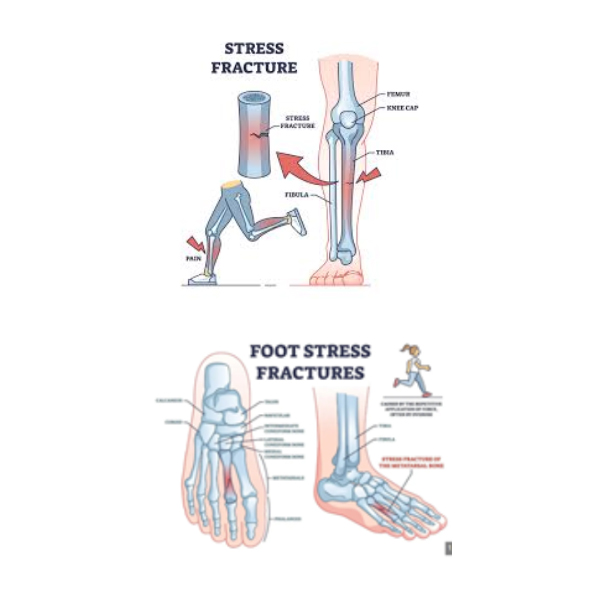

شکستگیهای استرسی

شکستگیهای استرسی، ترکهای کوچک و مویی شکلی هستند که در نتیجه نیروهای انباشته شده روی استخوان ناشی از فعالیتهای تکراری مانند دویدن یا پریدن در مسافتهای طولانی ایجاد میشوند. بدن دائماً بافت استخوان را تجزیه و بازسازی میکند. با این حال، هنگامی که ضربات کوچک مکرر از توانایی استخوان برای ترمیم خود فراتر رود، ترکهای میکروسکوپی در استخوان ایجاد میشوند.

شکستگیهای استرسی بیشتر در استخوانهای پا و ساق پا شایع هستند. بنابراین، یکی از علل شایع درد استخوان پا و ساق، شکستگی استرسی است. افزایش ناگهانی فعالیت بدنی، پوشیدن کفش نامناسب و شرایطی که تراکم استخوان را کاهش میدهند، مانند پوکی استخوان، خطر ابتلا به شکستگی استرسی را افزایش میدهند.